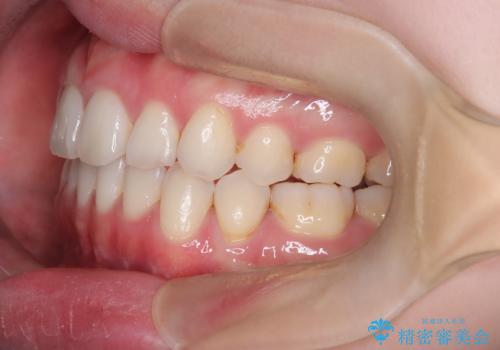

【抜歯インビザ】前歯の凸凹をなおしたい

- 前歯の凸凹を主訴に来院されました。

前歯はあまり下げる必要がなかったため、上下左右の第二小臼歯抜歯を行う治療計画としました。

途中、臼歯の近心傾斜を認めましたが、追加アライナーを使用することでリカバリーを行いながらインビザラインのみで治療を完了することができました。